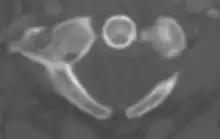

Atlas from above

The atlas's chief peculiarity is that it has no body,[3] which has fused with the next vertebra.[4] It is ring-like and consists of an anterior and a posterior arch and two lateral masses.

The lateral masses are the most bulky and solid parts of the atlas, in order to support the weight of the head.

Each carries two articular facets, a superior and an inferior.

- The superior facets are of large size, oval, concave, and approach each other in front, but diverge behind: they are directed upward, medially, and a little backward, each forming a cup for the corresponding condyle of the occipital bone, and are admirably adapted to the nodding movements of the head. Not infrequently they are partially subdivided by indentations which encroach upon their margins.

- The inferior articular facets are circular in form, flattened or slightly convex and directed downward and medially, articulating with the axis, and permitting the rotatory movements of the head.

Vertebral foramen

Just below the medial margin of each superior facet is a small tubercle, for the attachment of the transverse atlantal ligament which stretches across the ring of the atlas and divides the vertebral foramen into two unequal parts:

- the anterior or smaller receiving the odontoid process of the axis

- the posterior transmitting the spinal cord (medulla spinalis) and its membranes

This part of the vertebral canal is of considerable size, much greater than is required for the accommodation of the spinal cord.